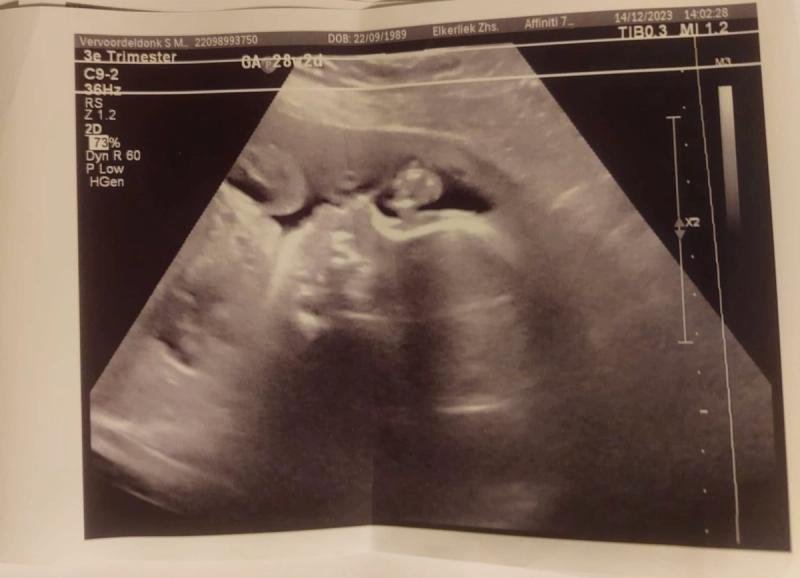

Een aantal dagen later heb ik een afspraak staan bij de gynaecoloog, die geeft aan dat het een oude infectie is die opnieuw actief is geworden. En dat minder schadelijk is dan een primaire infectie. Hij maakt zelf een echo van de baby en die doet het goed, hij lijkt niet zichtbaar last te hebben van CMV. De gynaecoloog geeft aan dat er allerlei symptomen bij een baby op kunnen treden. Van een zwaar gehandicapt kind tot een kind met gedragsproblemen.

De arts maakt een zeer uitgebreide echo

Ze gaan een echo maken, want een baby met een CMV infectie kan namelijk afwijkingen op de echo laten zien. Ik krijg een zeer uitgebreide echo en op het laatst geeft ze aan dat de baby er voor nu helemaal gezond uit ziet, maar dat dit alleen (nog) niks wil zeggen. De afwijkingen kunnen namelijk ook nog later zichtbaar worden. Ze gaan mij bespreken in een groot overleg en een uur later komen ze dan met een plan. Dit was een heel lang uur kan ik je vertellen…